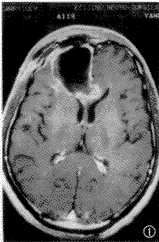

试验组术后反应性增强的发生率为74.6%(417/559)(图1~3),最早可出现在术后24h之内,其持续时间长短不一,最短者持续2个月,最长者可持续至术后9个月,平均6个月左右消失。在术后8~25d时增强最明显。术后残存肿瘤增强的发生率为24.2%(135/559)(图4~6)。有7例术后无增强,其中5例在术后24h之内行MR检查,2例分别在术后41 d和45 d时行MR检查。对照组术后反应性增强的发生率为85.9%(108/126)。因对照组术前无增强,其术后残存的发生率未统计。术后反应性增强与术后残存增强的影像学表现特点见表1。

图4~6 患者 男,45岁。右颞胶质母细胞瘤。术前病灶不规则环形增强,有囊变,占位征象明显(图4);术后1个月,术区边缘有结节状增强及轻度占位征(图5);术后8个月,术区周边原增强灶增大,水肿及占位征象明显。第2次手术证实肿瘤复发(图6);图5所示残存肿瘤的增强与术前增强部位无明显的对应关系